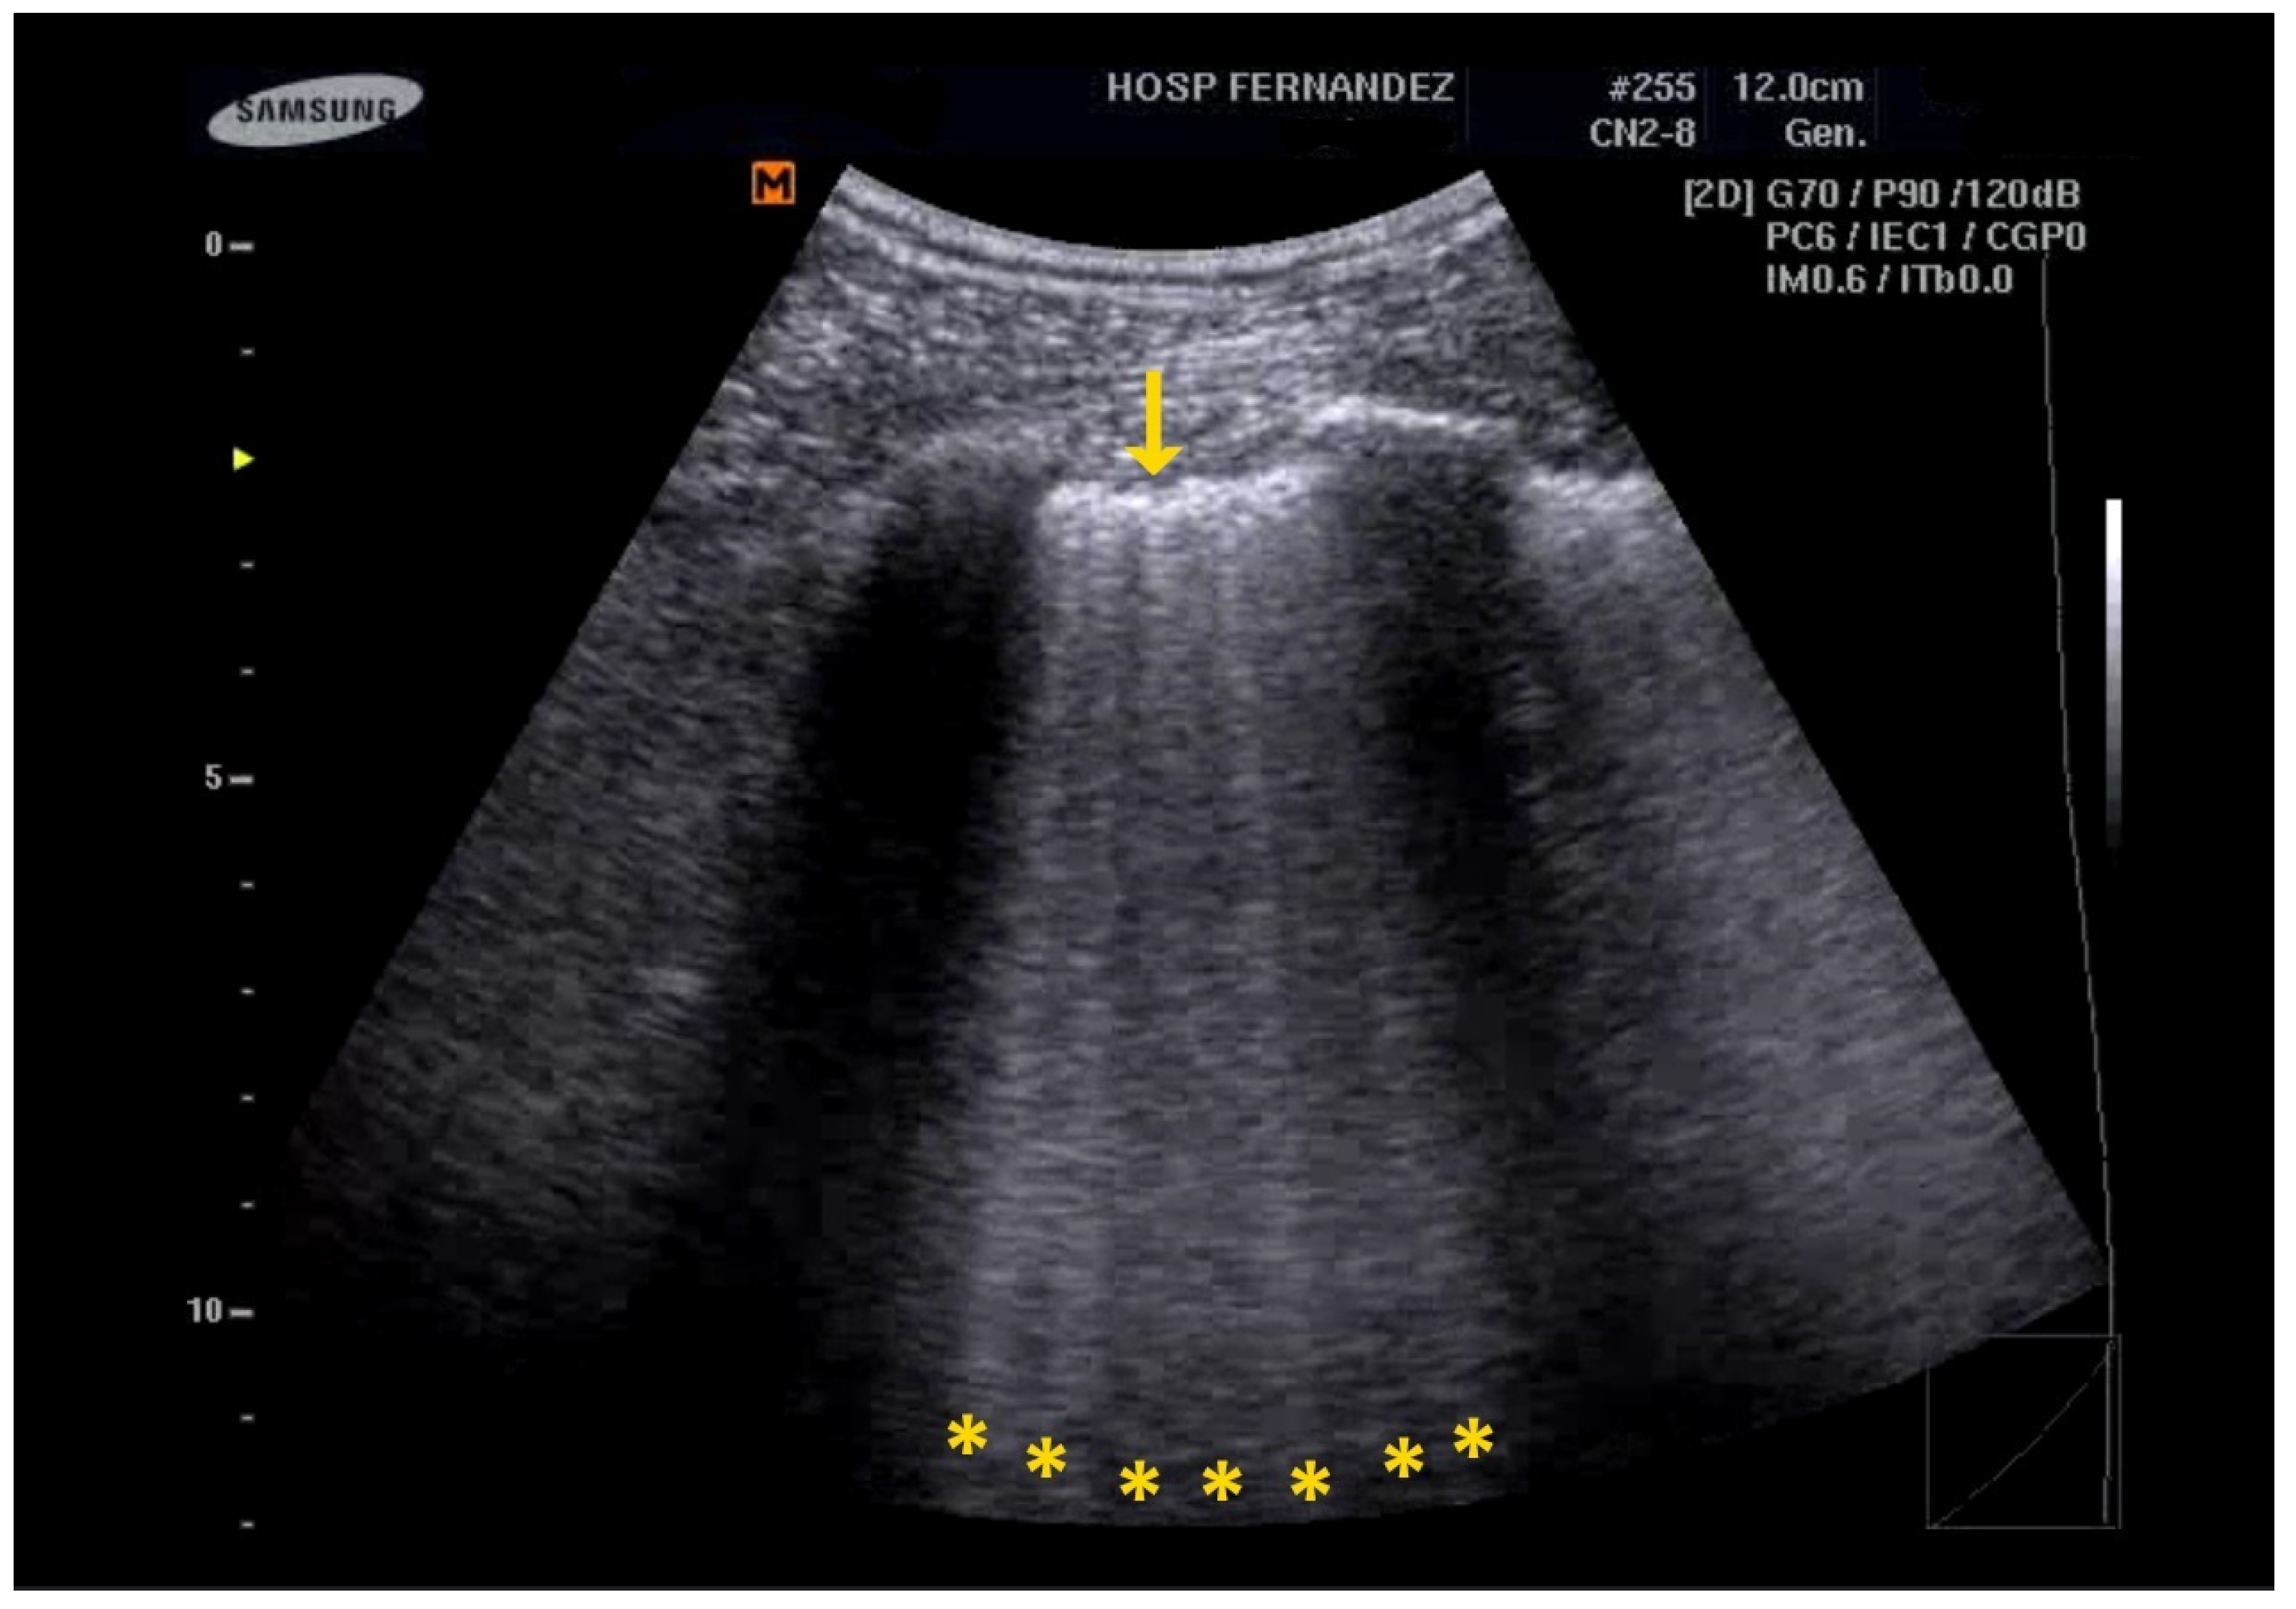

The count of observed B-lines has been proven to correlate more effectively with disease severity than high-resolution CT scans, demonstrating its utility not only in diagnosis but also in severity stratification. The latest iteration of the LUS scoring system differentiates between moderate and severe loss of aeration based on the percentage of the pleura occupied by artifacts, which may include spaced or coalescent B-lines or subpleural thickenings. A loss of aeration is classified as moderate if 50% or less of the visualized pleura is affected; conversely, if the affected area is clearly greater than 50%, it is classified as severe [22]. See Figure 1 and Clip S1.

Figure 1.

B-lines are hyperechoic artifacts descending from the pleural line to the bottom of the screen (yellow *).

The following supporting information can be downloaded at https://www.mdpi.com/article/10.3390/healthcare13101148/s1, Clip S1: B-lines are hyperechoic artifacts descending from the pleural line to the bottom of the screen (yellow *); Clip S2: Multiple B-lines and irregular pleural line (yellow * and yellow ↓); Clip S3: Subpleural consolidation (yellow ↓) “Shred sign”; Clip S4: Consolidations with an LUS score of 3 indicate a complete loss of aeration measuring greater than 2 cm (yellow *). In addition, the preservation of the vasculature can be detected by color Doppler. Clip S5: Consolidations with an LUS score of 3 indicate a complete loss of aeration of the entire inferior right lobe (yellow *).